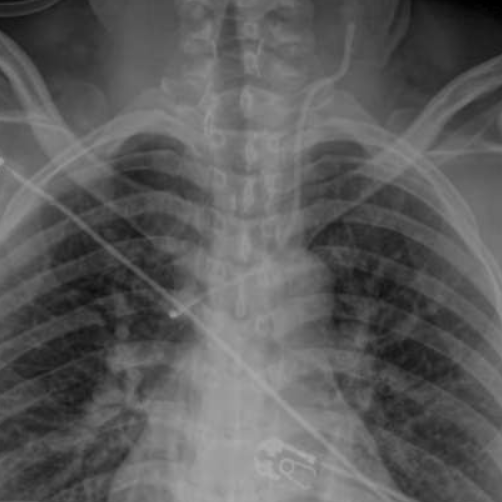

Patient to PACU, formal CXR and... now the line looks like it's possibly back in the azygous vein? The "down the barrel" view on CXR is a/w azygous placement, but I have no idea as to the specificity.